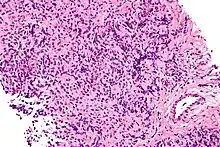

Micrograph of a primary mediastinal large B-cell lymphoma, a type of large-cell lymphoma. H&E stain.

The large-cell lymphomas have large cells. One classification system for lymphomas divides the diseases according to the size of the white blood cells that have turned cancerous. A large cell, in this context, has a diameter of 17 to 20 μm.[1] Other groups of lymphomas in this system are the small-cell lymphomas and mixed-cell lymphomas.